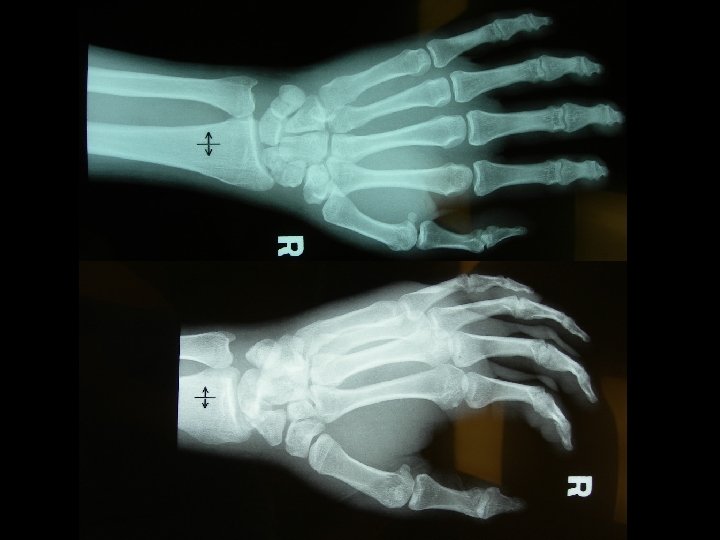

Question 2 • A 37 -year-old man attended A&E because of pain over his right wrist for one week after a fall from ladder. (a) What are the X-rays abnormalities?

Answer 2 a • Transcaphoid perilunate dislocation • Common in young adults • Fall on oustretched hand • Mechanism – bending with dorsal compression and tension on palmar surface owing to forced dorsiflexion

Perilunate Dislocation 60% with scaphoid fracture Radiolunate articulation is preserved Capitate dislocates almost always dorsal to the lunate capitolunate joint is disrupted, and the lunate projects through the space of Poirier • Proximal pole of scaphoid retains its articulation with the lunate, whereas the distal pole retains its relationship with the distal carpal row • • Image courtesy: http: //www. pt. ntu. edu. tw/hmchai/Kines 04/KINupper/Wrist. htm

Question 2 (b) What are the possible complications? • # scaphoid: – – AVN Non-union Secondary OA Sudeck atrophy • Perilunate dislocation: – – Median nerve palsy (carpal tunnel syndrome) Sudeck atrophy AVN Long-term carpal instability: Dorsal/Volar Intercalated Segment Instability (DISI/VISI) (c) What is your treatment? – Prompt ORIF